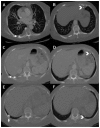

Bilateral mobile thoracolithiasis

Thoracolithiasis is the presence of one or more freely mobile pleural stones (with or without calcification) in the pleural space. They occur with a reported incidence of less than 0.1% and are benign and do not require intervention. Historically, they have led to unnecessary interventions - something unlikely in the era of multidetector computed tomography (CT). Thoracolithiasis should be included in the differential diagnosis of a single or multiple, mobile peripheral pulmonary nodules. Here, we review the imaging characteristics of a rare case of bilateral mobile thoracolithiasis.